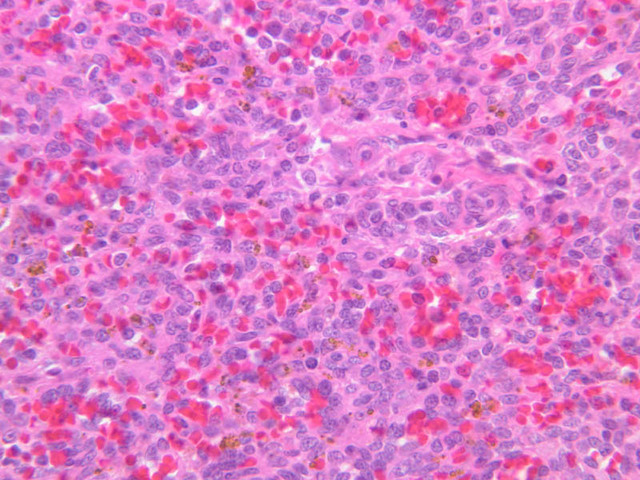

The remainder of the cellular mass in the spleen is red pulp (A-38 [10x, 20x, 40x]), made up of red and white cells of the blood enmeshed in the reticular tissue of splenic cords and present in the splenic sinuses. After passing through the PALS, the trabecular arteries branch to form smaller arterial vessels known as penicillar arterioles which narrow, forming arterial capillaries that empty into the cords of the red pulp (open circulation) or into the venous sinuses (closed circulation). In the splenic sinuses the cells of the blood are exposed to red pulp macrophages. The splenic sinuses eventually become confluent to form veins that enter the trabeculae and gradually merge meeting in the hilus to form splenic veins.

Examine the composition of the red pulp tissue. The three dimensional structure of the red pulp is analogous to Swiss cheese with the holes being the venous sinuses and the cheese being the parenchyma (i.e. splenic cords). On slide A-36 which is stained with Mallory's aniline blue locate examples of the splenic sinuses ([2.5x, 10x, 20x, 40x-labeled] [10x, 20x, 40x]). The walls of the splenic sinuses consist of adjoining specialized endothelial cells whose nuclei in many cases stand out from the wall in a bead-like fashion. The basement membrane of the epithelial cells stains blue revealing the sinuses quite nicely. Usually the sinus lumen is filled with red cells and leukocytes. The skeletal framework of the cords is provided by a network of reticular fibers. As above, the reticular cells are best seen using a reticular fiber stain (slide A-37 [2.5x, 10x, 20x, 40x-labeled]). Look for the large pale nuclei of reticular cells that have darkly stained reticular fibers. Fibers run irregularly in the cords, but clearly outline the sinuses around which they are wrapped. Notice on this same slide that there is much less reticular tissue in the white pulp than the red. The splenic cords occur around the sinuses and are distinguished by the presence of disintegrating red blood cells undergoing phagocytosis.

Here's a little histopathology: Observe slide A-40 (H&E [2.5x, 10x, 20x, 40x]). In this slide the corpses of red blood cells appear brown and can be seen littered throughout. These residual RBCs are referred to as hemosiderin. Slide A-39 (H&E [2.5x, 10x, 20x, 40x]) was prepared from a patient undergoing chemotherapy. How does the white pulp in this slide differ from the normal spleen, slide A-38?